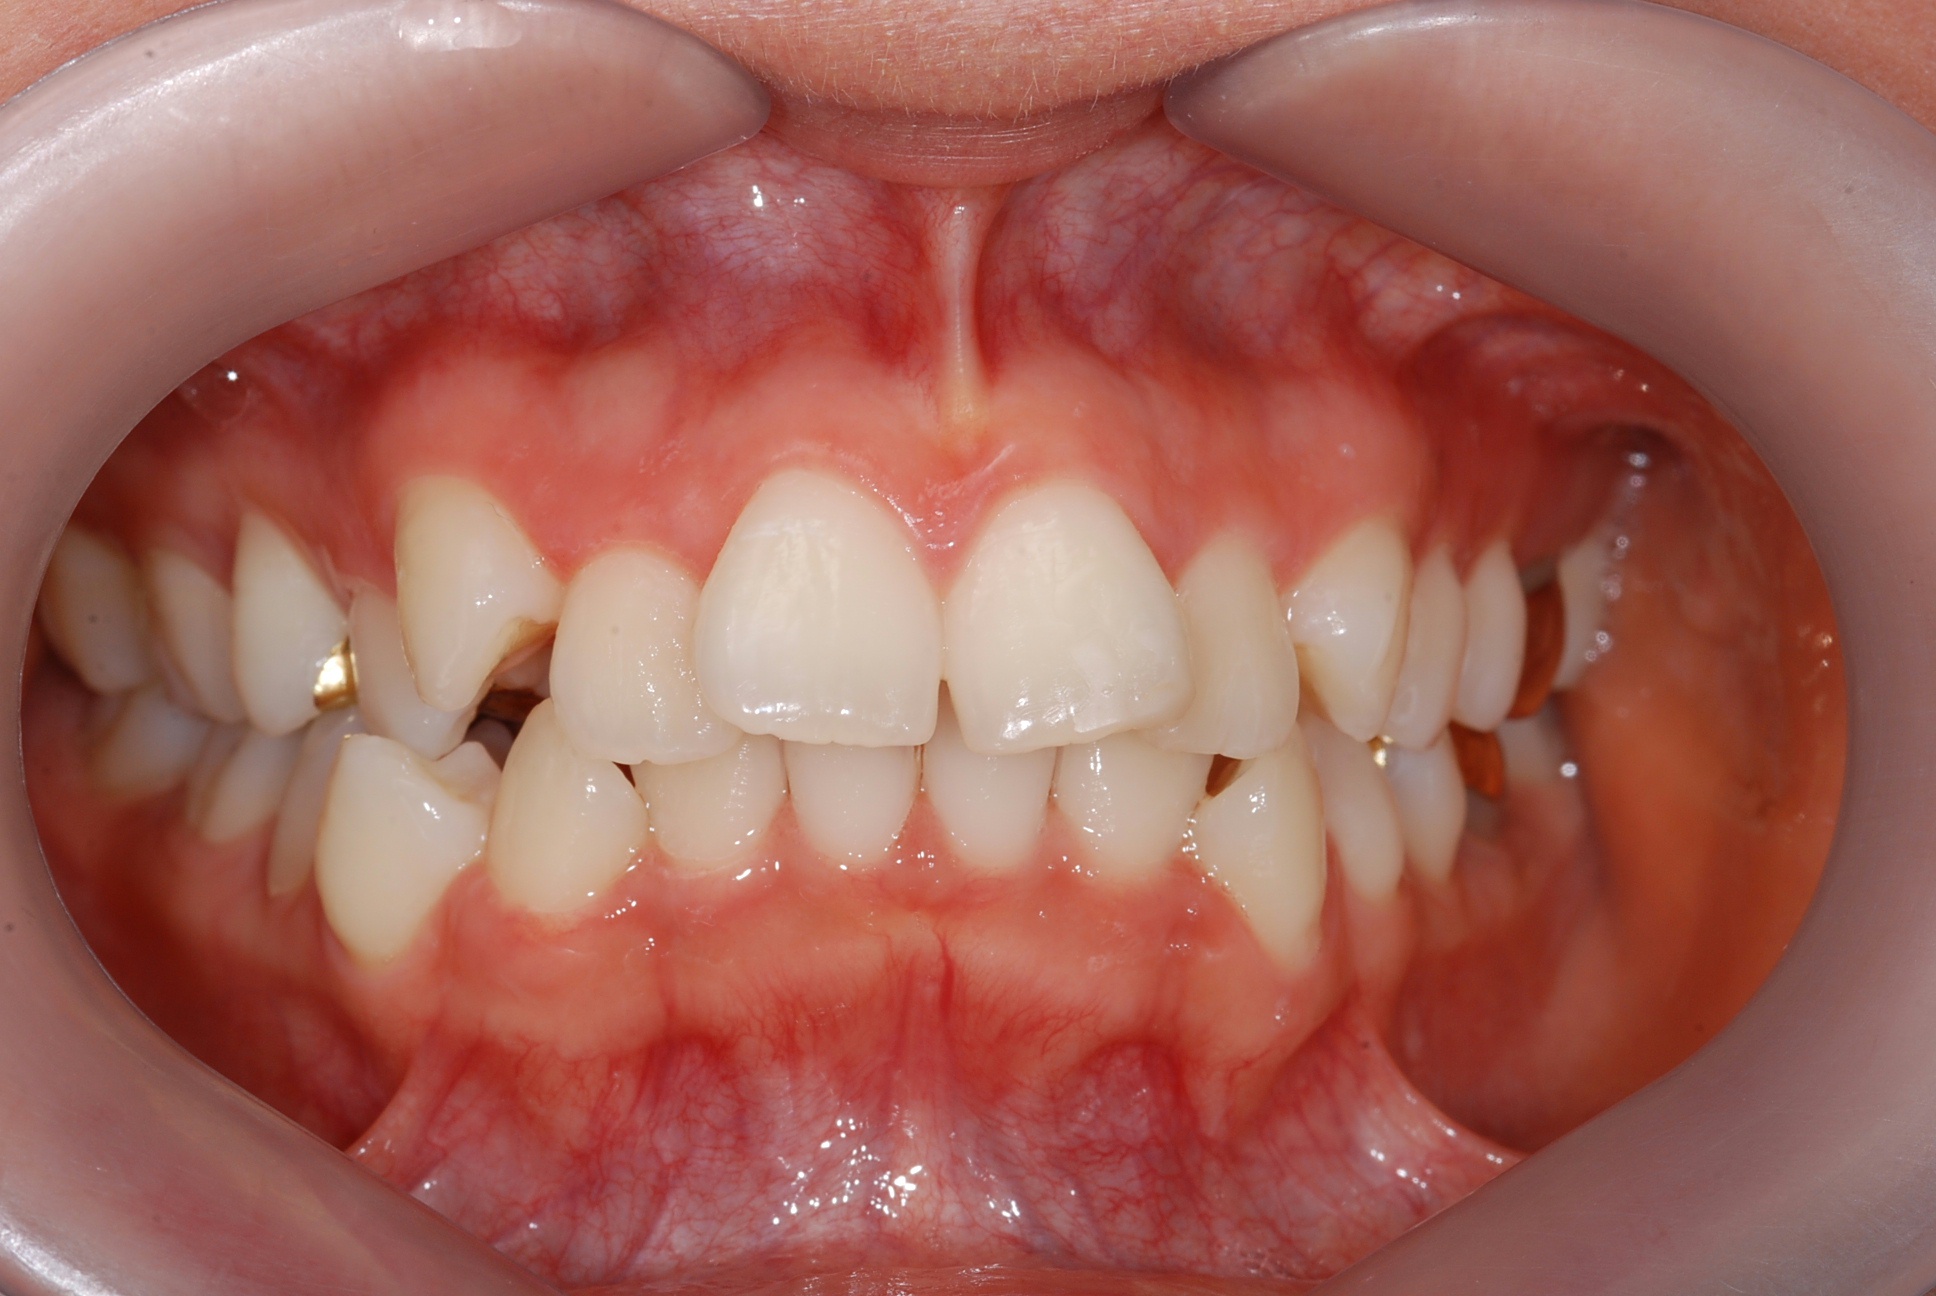

치료 전 사진입니다.